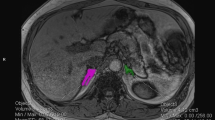

Primary aldosteronism (PA) is a common disease. Especially in unilateral PA (UPA), the risk of cardiovascular disease is high and proper localization is important. Adrenal vein sampling (AVS) is commonly used to localize PA, but its availability is limited. Therefore, it is important to predict the unilateral or bilateral PA and to choose the appropriate cases for AVS or watchful observation.

The accuracy of the machine learning was 88% and the top predictors of the UPA were plasma aldosterone concentration after the saline infusion test, aldosterone to renin ratio after the captopril challenge test, serum potassium and aldosterone-to-renin ratio. By using these factors, the accuracy, sensitivity, specificity and the area under the curve (AUC) were 91%, 70%, 99% and 0.91, respectively. Furthermore, we examined the surgical outcomes of UPA and found that the group diagnosed as unilateral by the predictors showed improvement in clinical findings, while the group diagnosed as bilateral by the predictors showed no improvement.